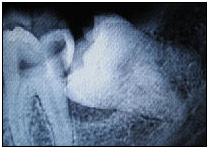

Wisdom teeth often cause no problems. They are described as impacted when there is not enough space for them at the back of the mouth. In such a case it might erupt towards the cheek or it might impinge on the second molar. Impacted wisdom teeth can cause pain, swelling, infection or damage to the teeth next to them. If the gum around the wisdom tooth is swollen the jaw may become stiff and sore. Infection at the back of the mouth can cause bad breath and a bad taste. The surgical removal (extraction) of one or more wisdom teeth can relieve these problems. People who have impacted wisdom teeth that are not causing problems do not need to have them removed.

The removal of such impacted wisdom tooth has to be accomplished surgically. A flap is reflected to completely expose the tooth. Some amount of bone cutting may be required to facilitate easy removal. After the tooth is extracted the flaps are put in place and sutured. The procedure is performed under local anesthesia and is associated with minimal pain and discomfort.